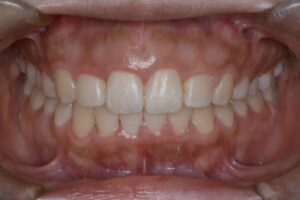

矯正治療終了